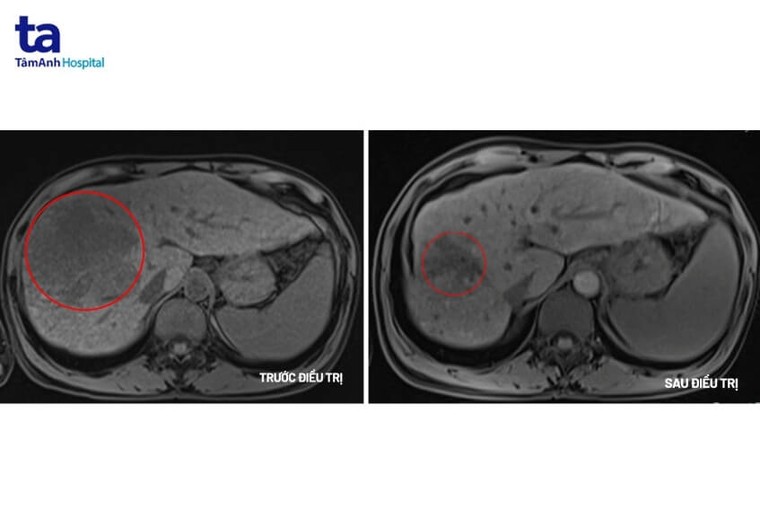

Xét nghiệm chỉ điểm ung thư gan cho thấy chỉ số AFP là 9412ng/mL (người bình thường chỉ số này là < 10ng/mL); AFP L3 81,3% (ngưỡng bình thường <10%); PIVKA II=56661 mAu/mL (ngưỡng bình thường <40 mAu/mL). Trên MRI cho thấy khối u lớn ở gan phải với kích thước 10x10x12cm có tính chất HCC, huyết khối tĩnh mạch cửa và xơ gan. Kết quả cho thấy người bệnh mắc ung thư gan giai đoạn muộn.

Sau 12 chu kỳ (khoảng 6 tháng) điều trị phác đồ miễn dịch kết hợp kháng thể đơn dòng, khối u gan đã giảm hơn 50% kích thước, người bệnh không xuất hiện triệu chứng đau, không có dịch ổ bụng, chức năng gan thận trở lại bình thường, cải thiện chất lượng cuộc sống. Bệnh nhân tiếp tục được điều trị và theo dõi chặt chẽ để nâng cao hiệu quả.

Hình ảnh khối u trước và sau điều trị. Ảnh: BVĐK Tâm Anh. |